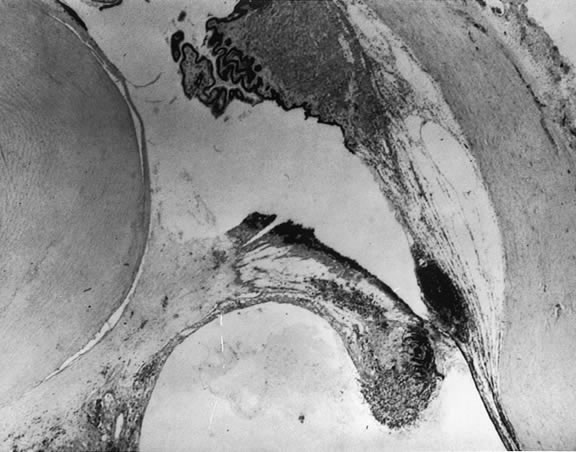

The vitreous body interfaces with a number of ocular structures through the vitreous cortex (Fig. 1). The vitreous cortex extends anteriorly from the vitreous base to form the anterior vitreous cortex and posteriorly to form the posterior vitreous cortex. Recently, the clinical importance of vitreous cortex has become increasingly apparent. The vitreous cortex has been implicated as a primary factor in a variety of vitreoretinal disorders, including retinal breaks, proliferative vitreoretinopathy (PVR), anterior hyaloidal fibrovascular proliferation, macular holes, and epiretinal membranes.

The anterior vitreous cortex or anterior hyaloid is the anterior surface layer or condensation of the vitreous body. There is no specialized membrane that constitutes the anterior vitreous cortex, but instead there is a greater density of collagen fibrils. Microscopically, the framework of collagen fibrils that run throughout the vitreous body ends in an interwoven network to form the anterior vitreous cortex. The superficial fibrils tend to run parallel to the surface in this region. The smooth surface and membrane-like appearance are due to the lamellar distribution of the cortical fibers and the associated highly polymerized mucoproteins.4,5 Anatomically, the anterior hyaloid forms the posterior limits of the posterior chamber. This portion of the vitreous cortex functions in the physiologic communication between the vitreous cavity and the aqueous humor. The anterior surface of the vitreous body separates from the pars plana approximately 1.5 mm anterior to the ora serrata. It extends medially to contact the lens posterior to the lens equator. Thus, the anterior hyaloid is in contact with the ciliary processes and the lens zonules, as well as the posterior lens capsule. The vitreous attaches to the lens capsule in a ring-like manner, forming the hyaloideocapsular ligament of Wieger. This ligament is believed by some to be synonymous with the attachment ring of the posterior zonular fibers.4 The circular area of attachment measures approximately 9 mm in diameter and is especially firm in younger persons or after intraocular inflammation.5 In this circular area the anterior hyaloid is thickened. Central to the attachment of Wieger's ligament (also known as Egger's line), the vitreous lens attachment is less pronounced and appears to be due to surface tension. This central area contains a potential space within the 9-mm ring known as Berger's space, or the patellar fossa. The anterior hyaloid then turns posteriorly to form the anterior portion of Cloquet's canal in the midportion of Berger's space. Cloquet's canal represents the remnants of the primary vitreous and can sometimes be seen with the slit lamp. It arises from the optic disc in a funnel-shaped manner, in the area of Martegiani, and extends forward to the posterior lens surface. The canal is 1 to 2 mm in width and has a down turn in the central vitreous cavity. The area of contact with the posterior lens capsule can at times be identified by a tag of embryonic tissue, known as a Mittendorf dot, located slightly nasal to the posterior pole of the lens. Similarly, a remnant of the posterior primary vitreous can occasionally be identified on the optic disc. This remnant, representing the embryonic point of exit of the hyaloid vascular system from the optic nerve head, is known as Bergmeister's papilla. The walls of Cloquet's canal are formed by a vitreous condensation rather than a true membrane (see Fig. 1).

The nature of the adhesion between the vitreous cortex and the ILM is enigmatic. This adhesion is strongest at the optic nerve, the macula, the vitreous base, and retinal vessels. Foos6 demonstrated attachment plaques between Müller's cell cytoplasm and the ILM in the basal and equatorial retina (Fig. 2). Vitreous traction mediated by vitreous fibrils may contribute to these adhesions. These attachment plaques are not present posterior to the equator except where the ILM is thinned in the fovea. This anatomic variation in the fovea region may play a role in the pathogenesis of some of the vitreomacular disorders.